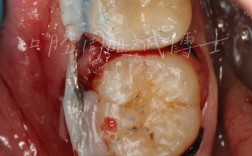

这是解决骨量不足最经典的方法,通过移植自体骨、人工骨等材料,增加牙槽骨的体积,待新骨成熟后再进行种植,常见技术包括:

引导骨再生术(GBR):

适合骨宽度/高度轻度不足(如缺牙区骨宽度仅5-6mm,而种植体需要8mm),医生会在骨缺损处覆盖“生物膜”(屏障膜),防止软组织长入,同时植入骨粉(人工骨或自体骨),引导自身骨细胞生长,填补骨缺损。

优点:适用范围广,效果稳定;缺点:需要二次手术(取骨或单独植入骨粉),愈合时间较长(通常3-6个月)。 -